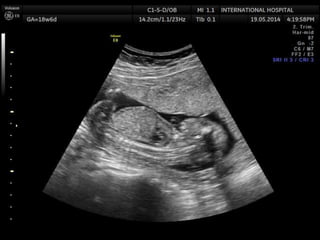

Edwards syndrome (Trisomy 18)

1st trimester

Increased nuchal translucency

2nd trimester

Multiple major anomalies

Single major anomaly + Trisomy 18 marker

Choroid plexus cyst + other anomalies

Early IUGR

IUGR

Cardiac defects

Muskuloskeletal findingd

-Clenched hands + overlapping index finger

Arthrogryposis

Rocker bottom foot

Clubfoot

Radial ray malformation

Cystic hygroma

Brain anomalies

Strawvberry shaped calvarium

Meningomyelocele

Facial anomalies

GI anomalies

SUA